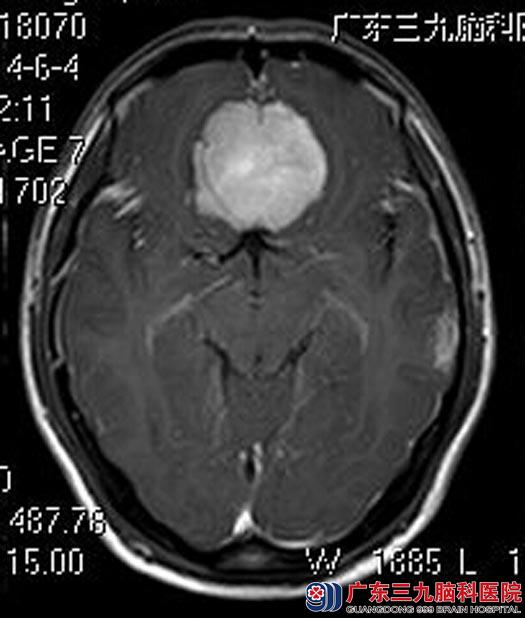

在广东三九脑科医院进一步MR检查提示:前颅窝底占位性病变,大小约45.3mm×46.9mm×26.4mm,头颅CTA提示:前颅窝底软组织肿块,血供丰富,双侧大脑前动脉A2段受压,其主干贴于肿块表面,右侧额极动脉部分段被包埋。

手术前